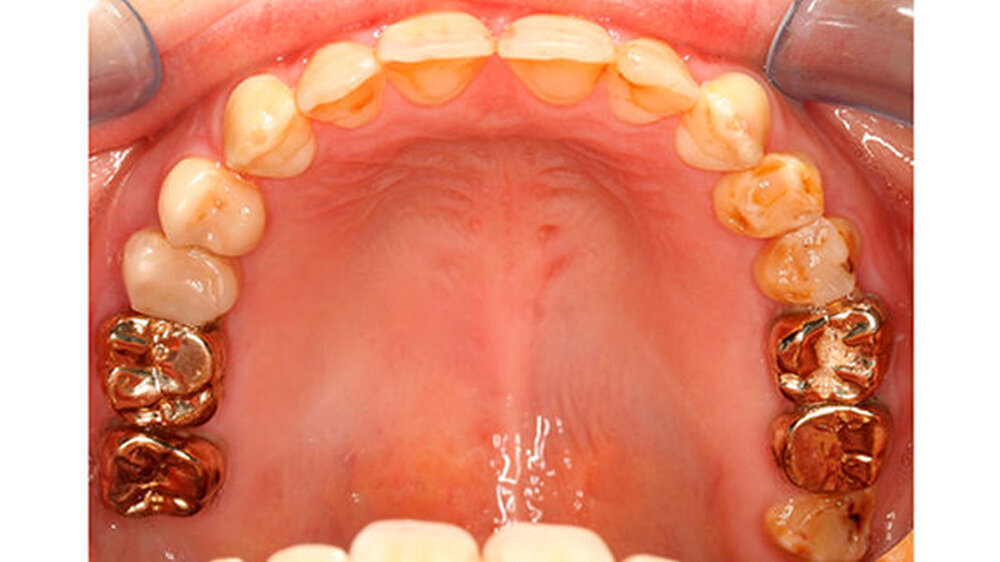

Mit dem Durchbruch der ersten bleibenden Molaren treten dann bisher unbekannte Beschwerden auf wie zum Beispiel eine übermäßig ausgeprägte Kälte-/Wärmeempfindlichkeit. Für manche Kinder wird dadurch nicht nur die Mundhygiene sondern auch die Nahrungsaufnahme erschwert. Zusätzlich bricht oft schon in der Durchbruchs-Phase der Schmelz ein (Abbildung 1), was die Überempfindlichkeit in teils akute Zahnschmerzen übergehen lässt.